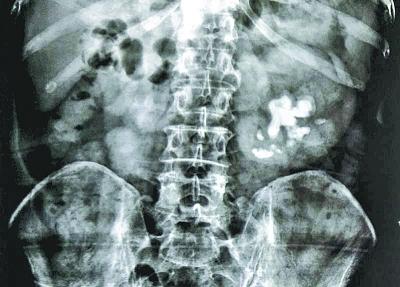

从1994年开始,王先生就因双肾小结石发作,陆续做过体外碎石、开刀取石、输尿管镜取石等治疗,后来不疼不痒就没管。谁知,最近再查右肾已萎缩无功能,而左肾结石竟长到7.2×3.3厘米大,像一朵盛开的白玉兰(见图)。若不及时取出,可能会面临双肾功能丧失,即我们常说的“尿毒症”。

近日,为避免情况恶化,他慕名赶到可以保肾取石的武汉京都结石医院。为确保手术安全和治疗效果,医院为他制定了清石率很高的“双镜联合微创保肾取石”的手术方案,成功将分散在各个盏腔的结石取出,至此,王先生的左肾危机得以解除。